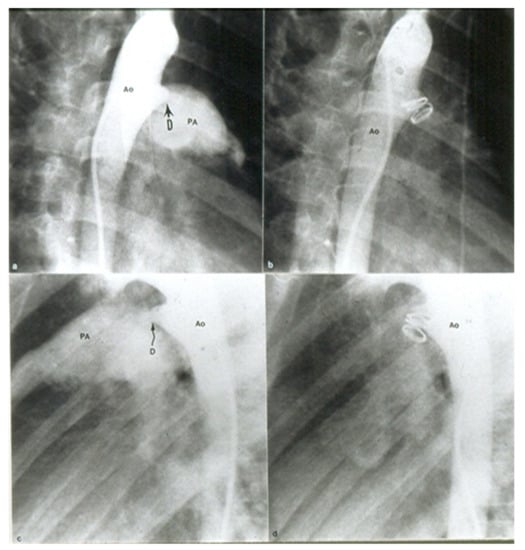

- Rao, P.S. Transcatheter occlusion of patent ductus arteriosus: Which method to use and which ductus to close? (Editorial). Am. Heart J. 1996, 132, 905–909. [Google Scholar]

- Rao, P.S. Coil occlusion of patent ductus arteriosus (editorial). J. Invasive Cardiol. 2001, 13, 36–38. [Google Scholar]

- Rao, P.S. Transcatheter closure of moderate-to-large patent ductus arteriosus (Editorial). J. Invasive Cardiol. 2001, 13, 303–306. [Google Scholar]

- Rao, P.S. Percutaneous closure of patent ductus arteriosus: State of the art (Editorial). J. Invasive Cardiol. 2007, 19, 299–302. [Google Scholar] [PubMed]

- Rao, P.S. Percutaneous closure of patent ductus arteriosus—Current status. J. Invasive Cardiol. 2011, 23, 517–20. [Google Scholar] [PubMed]

- Yarrabolu, T.R.; Rao, P.S. Transcatheter closure of patent ductus arteriosus. Pediatr. Ther. 2012, 5, 005. [Google Scholar] [CrossRef]